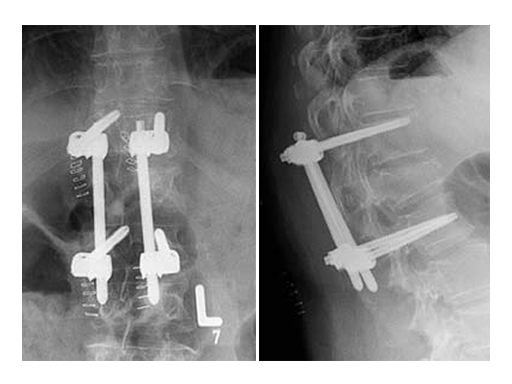

Based on the preoperative analysis and the surgical plan, the patient was positioned supine for the first surgery and the fracture was stabilized with a bridging construct (T12-L2) from posterior. Due to the ruptured disc, an anterior reconstruction of the spine was planned for a later stage surgery. The posterior stabilization was considered to be sufficient to bridge the fracture and time between both surgeries.

Using the USS Fracture MIS system for the initial stabilization allowed for a minimally invasive approach with intraoperative active reduction of the spinal fracture. The unique design of the fracture clamp allowed for independent correction of the sagittal alignment (Fig a) as well as height readjustment (Fig b).

For this patient, independent lordosis correction, height readjustment, and spinal stabilization were the primary goal of surgery. As percutaneous toploading pedicle screw systems cannot provide independent correction of the flexion-compression deformity, the fracture clamps and Schanz screws of the USS Fracture MIS system were used to overcome this disadvantage.

Due to the minimally invasive approach, the patient experienced less blood loss and muscle trauma compared to the traditional open approach.

Follow up CT Scans (AP, lateral and coronal) after the second surgery.